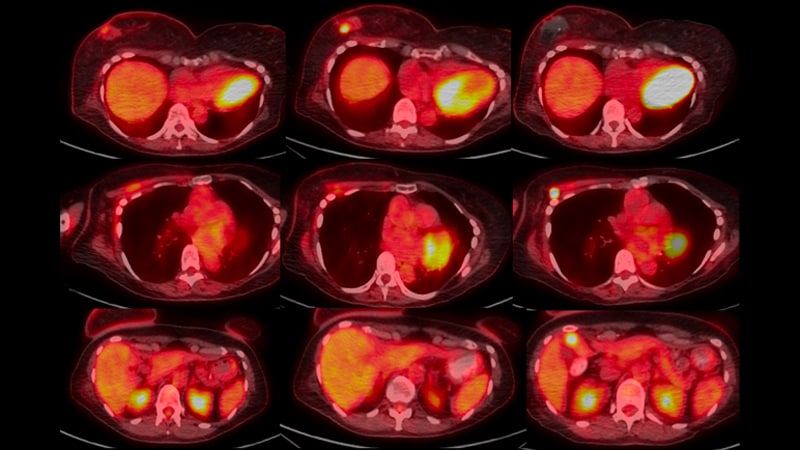

Metastatic Breast Cancer